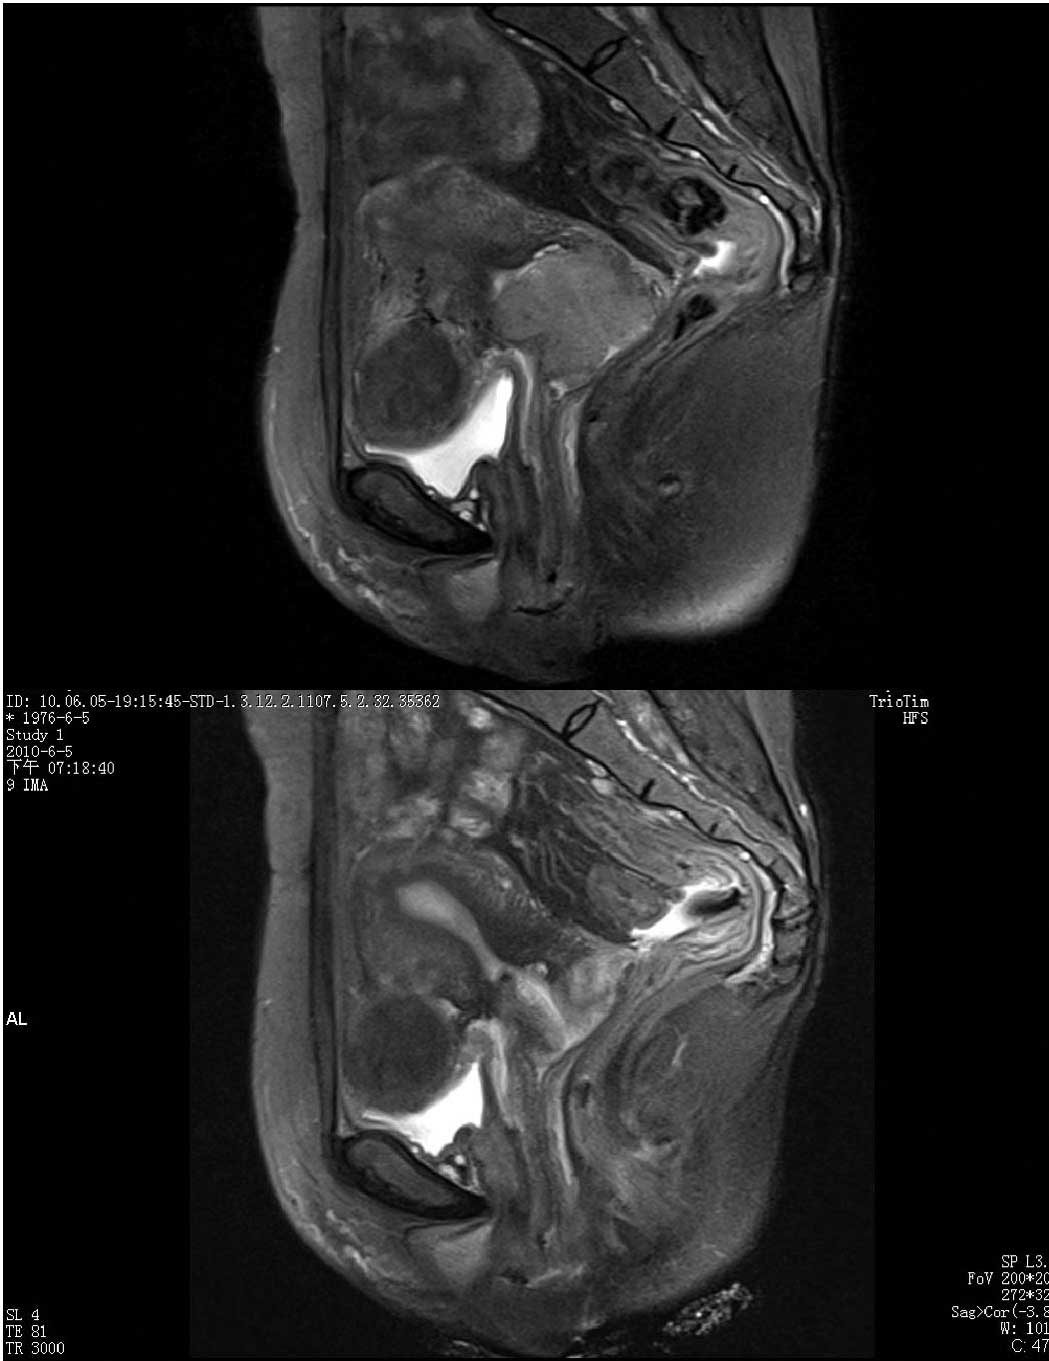

Treatment Of Early Bulky Cervical Cancer With Neoadjuvant Paclitaxel Carboplatin And Cisplatin Prior To Laparoscopical Radical Hysterectomy And Pelvic Lymphadenectomy

At first conversation with the oncologist all he kept telling us was that I needed a radical hysterectomy. However it is very important to note that recent studies have shown that women who have minimally invasive radical hysterectomies for cervical cancer have a higher chance of the cancer recurring and a higher risk of dying from the cancer than those who have. Design setting and participants.

We performed 321 type III open radical hysterectomies for cervical cancer between 2001 and 2013. Cancer survivors can be affected by a number of health problems but often a major concern is facing cancer again. 3-year survival rate for patients with stage IB to IIA cervical carcinoma after radical hysterectomy was 833 with an average life span of 328 months.

You have a history of cervical cancer or moderate to severe cervical changesContinue to have screening for 20 years after your surgery. Eighty-two patients with DSI LVSI or bulky SCC did not receive adjuvant therapy after radical. I am sorry to hear about your recent cervical cancer diagnosis and I hope you are recovering well after the radical hysterectomy.